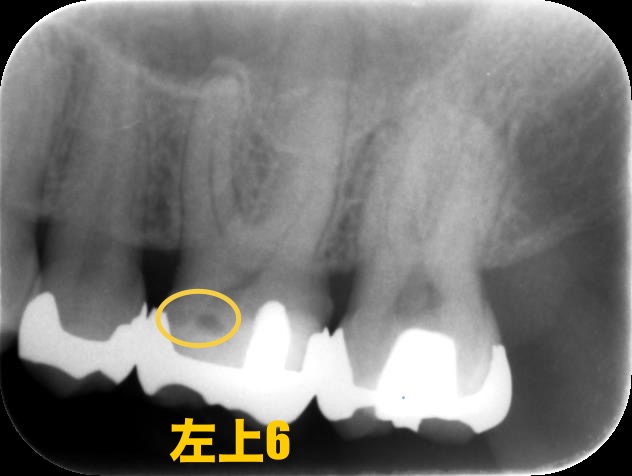

レントゲン写真、CTでも見てみましょう

黄色く囲っているところはカリエスで、青く囲っているところは根尖病変ができてしまっているところです。

この歯はレントゲン写真でもわかるほどカリエスの取り残しがありました。最初の治療でカリエスをきちんと取りきることが大切なのは大前提です。